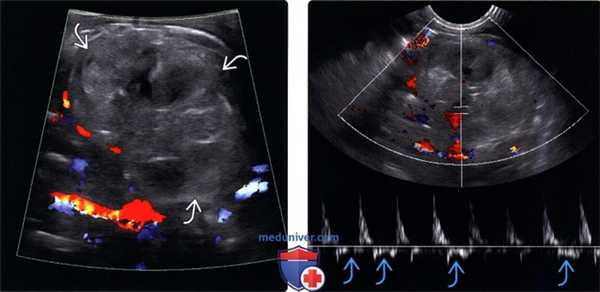

(Левый) На УЗ срезе с цветовой допплерографией левого верхнего квадранта живота у недоношенного младенца (33 недели) визуализируется гиповаскулярное образование неправильной формы. Образование практически не напоминало почку и на догоспитальном этапе было расценено как опухоль.

(Правый) При спектральной допплерографии у этого же пациента в почечной артерии визуализируется пандиастолическая регургитация вследствие острого тромбоза почечной вены. К сожалению, у этого младенца также было выявлено кровоизлияние в надпочечник с пораженной стороны (не показано).